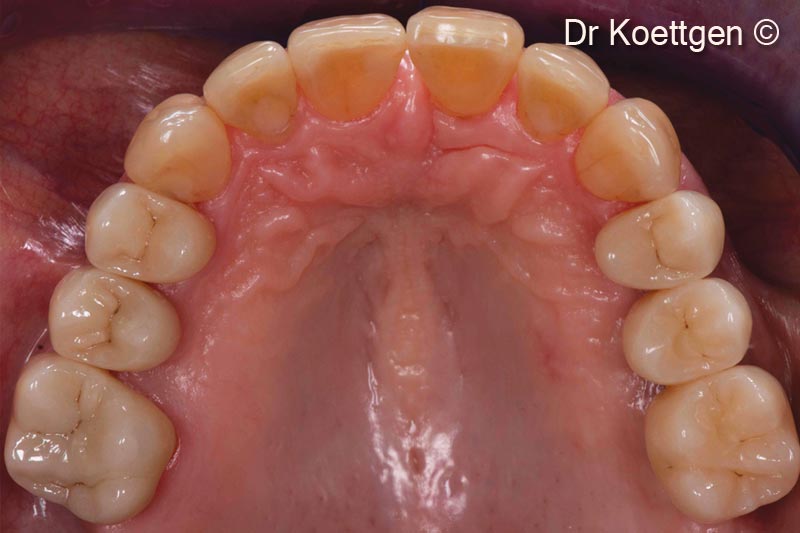

Phục hồi chức năng, nha chu, phục hình và thẩm mỹ phức tạp cho bệnh nhân bị viêm nha chu nặng

Sau khi nhổ răng, bệnh nhân nữ (63 tuổi) cần tăng cường mô cứng và mô mềm.